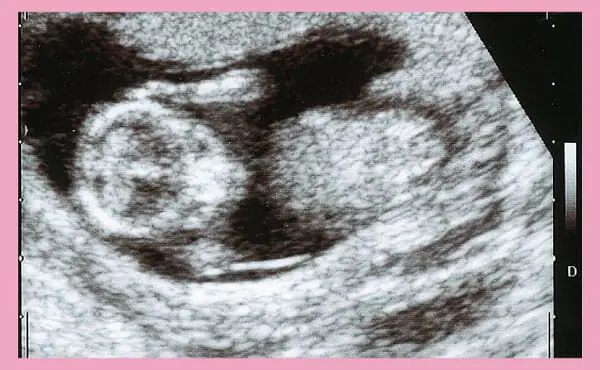

妊娠13週目のエコー写真です。